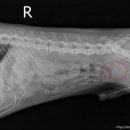

• 선부중앙동물의료센터 | 강아지 요로 결석 재발 재수술 후기

​ ​ ​ 강아지 결석 재발 재수술 후기 강아지 요로결석, 방광결석 재발로 재수술하게 된 후기 남겨봅니다. 반려견 결석은 재발률이 높은 편이라고 해서 꾸준히 관리...이번 수술은 선부중앙동물의료센터에서 진행했어요. ​ ​ ​ ​ 📍선부중앙동물의료센터 정보 주소 : 경기 안산시 단원구 선부광장1로 69 단지내상가동 2층...

참지않는 치와와(2026-03-28 13:21:00)